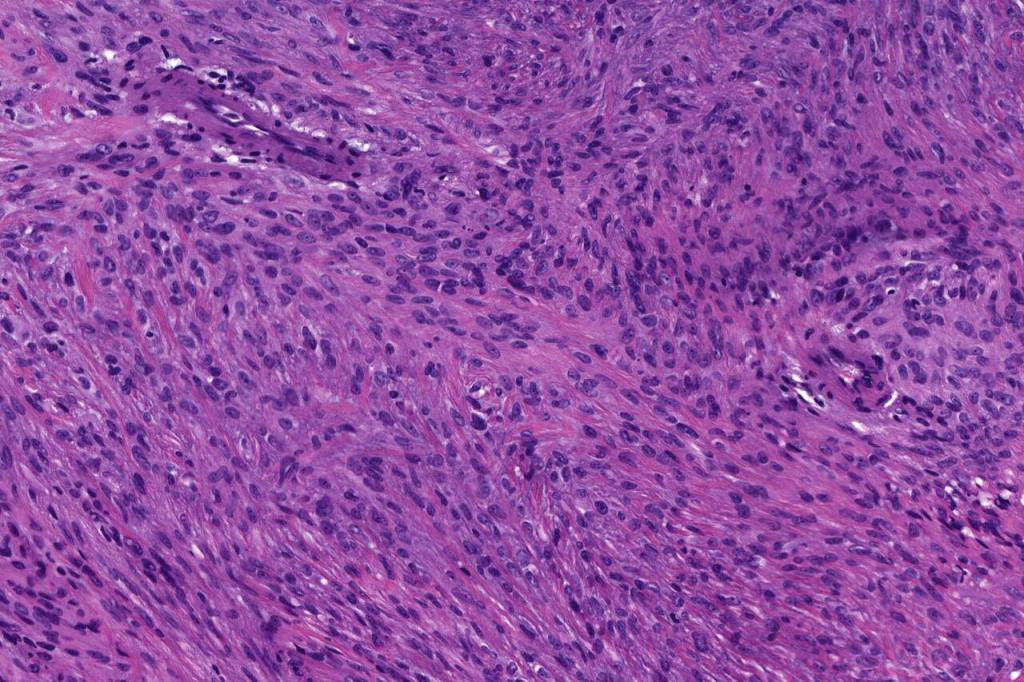

•Pure population of myoepithelial cells dispersed in sheet-like, reticular, whorled or fascicular patterns in a myxoid or hyaline stroma

•Cell types include epithelioid, spindled, histiocytoid & plasmacytoid

•Syncytial myoepithelioma characterized by sheet-like growth of ovoid to spindle cells with pale cytoplasm, syncytial borders & vesicular nuclei

•In malignant myoepithelioma there is an infiltrating border, marked pleomorphism, high mitotic rate & necrosis. Perineural infiltration & lymphovascular invasion may be seen